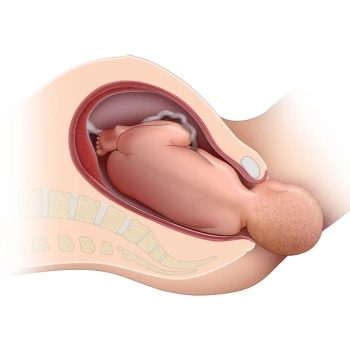

Is pregnancy care available for high-risk cases?

Absolutely, our experienced gynecologists specialize in managing high-risk pregnancies with advanced care and constant monitoring.